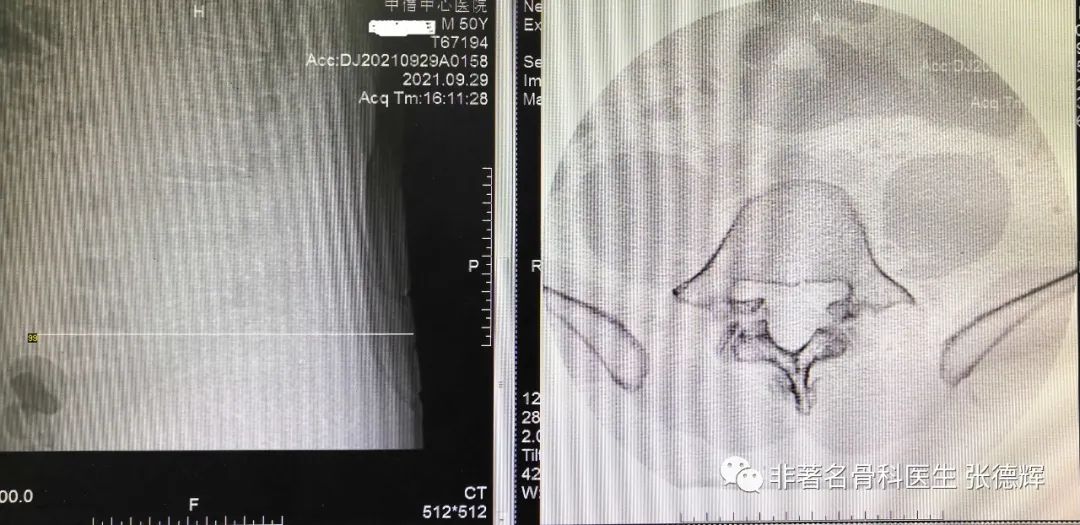

近期接诊一位腰椎峡部裂的患者,体重接近100公斤,腰腿痛近1年,严重时行走障碍,以下是影像检查资料。可以看到是明显的 腰5双侧峡部裂并轻度滑脱 。

腰椎CT密扫可见腰5双侧峡部骨质结构不连续